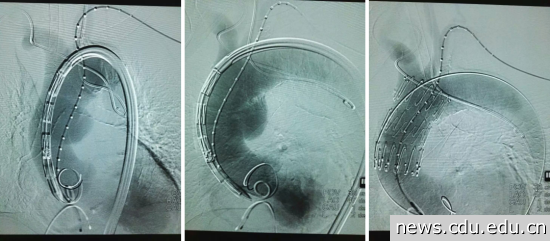

接受手术的是一名近80岁女性患者,该患者28岁即确诊类风湿性关节炎,长期受病痛折磨不得不每日口服激素及洛索洛芬钠抗炎镇痛治疗至今,患者在外院及附属医院确诊冠心病、主动脉瓣重度关闭不全、慢性心力衰竭、2型糖尿病,高血压病,脑梗塞、慢性肾功能不全等多系统危重疾病。患者多次因胸闷胸痛不适住院治疗,并曾因诱发恶性心律失常行电击复律,几度被告知病危。2016年4月,患者因胸痛来院就诊,CT血管造影术提示“升主动脉夹层动脉瘤伴升主动脉瘤样扩张,瘤壁菲薄,瘤体呈现囊袋状,长径约4cm,对周围大血管压迫效应明显”,病情极其危重,一旦动脉瘤破裂就会发生心包填塞、心跳骤停或失血性猝死。

4月29日,介入手术在介入室如期进行,术中探查见患者双侧股动脉多发粥样硬化斑块,通路建立困难,与患者家属沟通征得同意后,迅速改髂动脉入路建立血管通道,置入导管造影明确定位,交换导丝置入支架。在治疗团队的努力和精准定位下,支架释放一蹴而就,再次造影见位置准确,破口封闭良好,瘤体显影明显浅淡,观察后再次造影,瘤体几近消失。